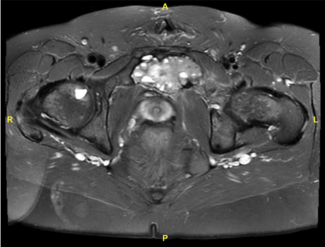

This report describes the development of a pubic aneurysmal bone cyst in a transgender patient who had previously undergone PIV, possibly indicating a very rare complication of this gender-affirming operation.